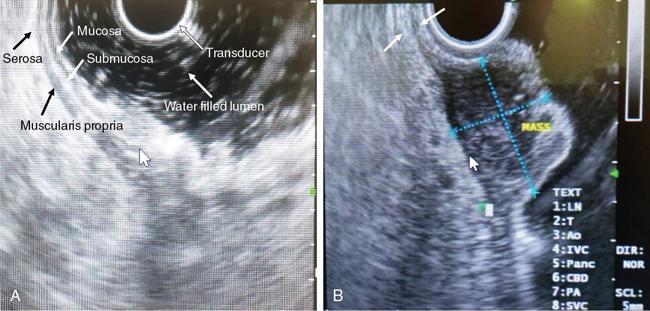

Swarup Nellore, Soumil Vyas, Ujwal Bhure, Ankit Jain, Richa Kothari, Daksh Mehta, Divya Kantesaria, Disha Lokhandwala, Karthik Ganesan The stomach is the most dilated portion of the gastrointestinal tract positioned between the oesophagus and the small intestine occupying the epigastrium, left hypochondrium and umbilical regions of the abdomen performing a multitude of functions including storage and mixing of food and controlling the passage of food into the intestine. Anatomically, the stomach is divided into the following parts (Fig. 8.2.1): the gastric cardia is the portion immediately adjoining the oesophageal opening into the stomach. The fundus is the dome-shaped part above the horizontal plane of the cardiac orifice which undergoes receptive relaxation and is the site of the autonomic pacemaker. The body is the largest part of the stomach extending from the cardiac orifice to the level of incisura angularis (notch like bend in the mid lesser curvature) containing majority of parietal cells (which secrete hydrochloric acid), chief cells (pepsinogen) and enterochromaffin-like cells (ECL). The pylorus is the tubular distal portion of the stomach which is further divided into the gastric antrum and pyloric canal. The pyloric antrum containing G-cells producing gastrin extends from the incisura angularis up to the pyloric sphincter which is an anatomical sphincter formed by concentric thickening of the circular muscle coat and encircles the narrow-slit like pyloric canal. The left dome of diaphragm and oesophagus lie superior to the stomach while the greater omentum and pancreas lie inferiorly. Spleen and liver lie on either side laterally while the transverse mesocolon is located inferolaterally. Diaphragm, greater omentum, left lobe of liver and anterior abdominal wall are anteriorly related to the stomach and contents of lesser sac including pancreas, spleen, splenic artery, transverse mesocolon, left kidney and adrenal gland lie posteriorly. The stomach is embryologically derived from the primitive foregut and is suspended anteriorly by the ventral mesogastrium and posteriorly by the dorsal mesogastrium. During development as the stomach rotates, the peritoneum grows and condenses to form perigastric ligaments, which contain blood vessels, lymphatics, lymph nodes, nerves and fat. The liver forms in the ventral mesogastrium, which develops into the falciform ligament, gastrohepatic ligament (GHL) and hepatoduodenal ligament (HDL). The spleen and pancreas form within the dorsal mesogastrium, which fuses with the posterior abdominal wall to form the gastrocolic ligament (GCL), gastrosplenic ligament (GSL) and splenorenal ligament (SRL). The perigastric ligaments are identified anatomically by the vessels contained in them (Fig. 8.2.2). The gastric cardia and lesser curvature of the stomach are attached to the inferior surface of liver by the lesser omentum by the gastrohepatic ligament respectively which contains the left and right gastric vessels. The inferior free edge of the gastrohepatic ligament extends inferiorly as the hepatoduodenal ligament between the porta hepatis and proximal duodenum gastrophrenic ligament extends between the stomach and the left hemidiaphragm. The gastrocolic ligament identified by the left and right gastroepiploic vessels, connects the greater curvature of the stomach to the anterior surface of the transverse colon. This ligament extends inferiorly as the greater omentum which is a double-layered peritoneum forming a drape anterior to the bowel loops. The gastrosplenic/lienogastric ligament bridges the posterolateral wall of the fundus and greater curvature along the proximal body of the stomach to the splenic hilum and contains the short gastric vessels. The gastrosplenic ligament is contiguous with the lienorenal ligament and both these structures constitute the lateral boundary of the lesser sac. Macroscopically the stomach shows a thick vascular mucosal lining in the form of longitudinal folds called gastric rugae. Microscopic layers of the stomach include mucosa, submucosa, muscularis externa and serosa. The mucosa includes surface mucus cells with simple columnar epithelium, gastric pits, gastric glands, lamina propria and muscularis mucosa. Submucosa includes connective tissue with submucosal Meissner’s plexus. Muscularis externa comprises three smooth muscle layers (longitudinal, circular and oblique) and Auerbach myenteric plexus. The outermost layer called serosa consists of loose connective tissue and visceral peritoneal lining. The arterial supply of stomach is constituted by the branches of celiac artery predominantly in the form of two anastomotic arcades along the lesser and greater curvature. Left gastric artery, a direct branch of the celiac trunk supplies the upper part of the lesser curvature while the lower part is supplied by the right gastric branch of the common hepatic artery arising at the upper border of pylorus. The left gastroepiploic artery, a branch of splenic artery, supplies the upper part of greater curvature and the inferior portion is supplied by the right gastroepiploic artery which is a branch of the gastroduodenal artery. The fundus additionally receives few small short gastric branches from the splenic artery. The veins follow the arteries in their nomenclature. Left and right gastric vein show direct drainage into the portal vein. The splenic vein derives flow from the short gastric and left gastroepiploic vein whereas the right gastroepiploic vein drains into the superior mesenteric vein. Pylorus can be surgically delineated by the prepyloric vein of Mayo lying on its anterior surface. Intrinsic nerve supply consists of the myenteric plexus of Auerbach and submucosal plexus of Meissner. Extrinsic nerve supply consists of sympathetic and parasympathetic components. Sympathetic nerve supply arises from T5 to T9 spinal cord segments supplying the celiac plexus via the greater splanchnic nerve. The plexuses then travel along the respective branches of celiac artery supplying the stomach. Parasympathetic nerve supply is derived from oesophageal plexus of vagus dividing into two vagal trunks. Right (posterior) vagus gives off the posterior gastric branch also called the criminal nerve of Grassi supplying the cardia and fundus of stomach. Right vagus then gives off a celiac branch and continues along lesser curvature of stomach as the posterior gastric nerve of Latarjet supplying the antrum, body and pylorus. Left (anterior) vagus gives off a hepatic branch then continues along the lesser curvature as the anterior nerve of Latarjet supplying the antrum, body and pylorus. Crow’s feet innervation to antropyloric area are important surgical landmarks preserved during highly selective vagotomy receiving branches from both major nerve trunks (anterior and posterior) at the incisura angularis. Anatomical lymphatic drainage is divided into three areas. Area I is the superior two-thirds of stomach draining via the nodes along left and right gastric vessels into the aortic nodes. Area II includes the right two-thirds of the inferior one-third which drains through the nodes along right gastroepiploic vessels via the subpyloric nodes into aortic nodes. Area III includes left one-third of greater curvature draining via short gastric and splenic nodes into suprapancreatic nodes and ultimately into aortic nodes. Gastric lymph node stations are divided into 4 levels with 16 lymph node stations: Paraesophageal nodes below the diaphragmatic hiatus (17) and above the diaphragmatic hiatus (18) are also included. The stomach first appears as a fusiform dilatation in the distal endodermal foregut in the 4th week of embryonic life. The dorsal and ventral mesogastrium suspend the developing stomach to the respective abdominal walls. Preferential growth along the dorsal border of the developing stomach leads to the formation of a convex dorsal border (greater curvature) and a concave ventral border (lesser curvature). The stomach subsequently undergoes a sequence of rotations. The first (90 degrees) clockwise rotation occurs around the longitudinal axis which brings the lesser curvature to the right and greater to the left. This rotation also brings the dorsal mesogastrium towards the left and ventral to the right creating a space behind the stomach called as the lesser sac or omental bursa. The second clockwise rotation occurs around the anteroposterior axis, with the caudal or pyloric part moving upwards and to the right while the cephalic or cardiac portion moves towards the left and slightly downward causing the stomach to assume its final anatomic position. This rotation causes the dorsal mesogastrium to bulge downwards and grow further to eventually become a double-layer apron called the greater omentum. The developing liver divides the ventral mesogastrium into the falciform ligament extending from the ventral abdominal wall to the liver with its lower free edge forming the ligamentum teres, the visceral peritoneum surrounding the liver and the lesser omentum with its two parts – the hepatogastric ligament and hepatoduodenal ligament. The dorsal mesogastrium gives rise to the redundant greater omentum, gastrocolic ligament, gastrosplenic ligament and lienorenal ligament. These perigastric ligaments help us in deciphering patterns of the spread of gastric malignancies and in taking decisions regarding their management and prognostication. These will be further explained in detail under the section of gastric malignancies. An abdominal radiograph is often the initial imaging test for evaluation of acute abdominal pain. The gastric bubble is seen below the left hemidiaphragm in situs solitus. Presence of gastric outlet obstruction may show a distended stomach with gasless small bowel. Hollow visceral perforation is diagnosed by free air seen under domes of diaphragm. Also, the presence and position of various tubes like the nasogastric tube can be confirmed using a radiograph. A fluoroscopic upper gastrointestinal (GI) examination is the radiological study of oesophagus, gastro-oesophageal junction, stomach, duodenum up to duodenojejunal junction by oral administration of contrast. Barium sulphate is a good contrast medium for GI studies as it is radio-opaque, non-absorbable, inert to tissues and can be used for double-contrast studies. Patient should be nil by mouth at least 4 hours prior to the examination. In a single contrast examination, the emphasis is on mucosal relief, luminal distention with contrast material and compression. In the erect position, a small amount of contrast is given to swallow while the oesophagus is visualized under fluoroscopy. The table is then made horizontal and the patient is rotated in a clockwise manner as seen from the foot end of the patient, thus ensuring good coating of the stomach mucosa. Mucosal relief images are then obtained in supine and prone positions to demonstrate the mucosal fold pattern and possible filling defects. After giving some more contrast, the patient is turned oblique with the right side dependent and spot images of the duodenal cap and C loop are taken both in distended and empty states. The patient is again positioned erect and more images of duodenal cap and loop are taken. Further contrast is given to optimally distend the lumen and assess for possible contour abnormalities, wall rigidity and strictures. Compression techniques help assess for filling defects and lesions, in the compressible areas of the stomach. Images are taken in multiple positions – supine, prone, right anterior oblique, right lateral, left posterior oblique in recumbent and right anterior oblique in erect position. Gastric peristalsis and emptying can be observed at fluoroscopy. Advantages of the single contrast technique are that it can be performed quickly, well-tolerated and requires less patient cooperation as compared to double-contrast studies. It can even be performed in physically debilitated patients. Barium is contraindicated in suspected cases of perforation, aspiration, fistula or recent GI biopsy. Single contrast examination can be performed using water-soluble iodinated contrast media in these cases and immediate postoperative patients. Earlier, ionic contrast like Gastrograffin was used. However, due to its high osmolarity, nowadays, non-ionic contrast is preferred as it causes less electrolyte imbalance due to its low osmolarity. Also, it delineates the GI tract very well due to less dilution. Double-contrast studies provide better evaluation of the mucosa than do single-contrast studies. Here, the emphasis is on coating the mucosa with barium and distending the lumen with gas. A well-performed double-contrast study is biphasic and also incorporates some single-contrast techniques. The initial part of the examination is the same as a single contrast examination to obtain the mucosal relief images. Then, gas-forming powder that produces carbon dioxide within the stomach lumen is given with more barium. With the double-contrast technique, the mucosa is coated with a high-density barium suspension and the lumen distended with gas. The patient is rotated in a clockwise manner as seen from the foot end of the patient, thus ensuring good coating of the stomach mucosa. Spot images of the distended stomach are taken followed by the duodenal cap and loop in oblique right-side dependent position. Patient is brought back to erect position erect and more images of stomach, duodenal cap and loop are taken. Further contrast is given to distend the lumen. Residual fluid or food debris in the stomach impairs stomach coating, and lack of adequate coating may preclude visualization of lesions. In addition, optimal gaseous distention is important as underdistention will cause a false appearance of abnormally thickened, and overdistention can obliterate abnormal folds. With normal gastric anatomy, the gastric fundus is best visualized in the upright left-posterior-oblique position, the body in the supine anteroposterior position and the antral-pyloric region in the supine left-posterior-oblique position. The normal gastric mucosal surface should be smooth on double-contrast studies. Areae gastricae appear as reticular networks of polygonal tufts which, owing to the presence of barium in the narrow intervening grooves, are coated with white lines. These are seen most often in the antrum or body of the stomach but can also be seen in the fundus. Areae gastricae are identified on double-contrast studies in 70% of patients and are seen more often in elderly patients. Polygonal tufts should normally range in size from 2 to 3 mm in the antrum and 3 to 5 mm in the body and fundus. Normal gastric folds are more prominent in the proximal to mid stomach and more undulating along the greater curvature as compared with the lesser curvature. Antral folds should be typically effaced with the double-contrast technique. Gastric cardia is characterized by three or four stellate folds radiating from a central point at the gastro-oesophageal junction; this is known as the cardiac rosette and is best visualized in the supine right-lateral position. Ultrasonography (USG) is the modality of choice to visualize hypertrophic pyloric stenosis in infants. Although USG does not play much of a role in adults for imaging of stomach due to reflection of sound waves by air, luminal distension with water may enable to identify mucosal – submucosal pathologies and to assess perigastric relationships in pathologies. CT can not only evaluate the location and anatomy of the stomach, but also provide additional information about the relationship of the stomach to surrounding structures. An optimal CT examination of the stomach includes good stomach distension with a well-visualized wall. Gastric distention can be achieved by the oral administration of negative or positive luminal contrast. Positive contrast agents include a 1%–2% barium suspension or a 2%–3% solution of a water-soluble iodinated contrast agent. Water-soluble agents should be used in cases of suspected perforation. Positive agents provide a bright lumen with better identification of luminal encroachment or diverticula but may limit detailed evaluation of gastric wall enhancement. Positive contrast also may not mix well with gastric contents, producing a pseudotumor appearance. On the other hand, neutral or negative contrasts agents, usually water, produce a low attenuation lumen which allows for more detailed evaluation of the gastric wall and its enhancement pattern following intravenous contrast and is preferred for three-dimensional imaging. Multidetector CT with thin collimation allows for postprocessing in any orthogonal plane. The CT data of the stomach can be manipulated to simulate endoscopic images (virtual gastroscopy). This display technique accentuates the stomach wall and folds. Prior to evaluating the stomach with CT, oral contrast is administered at repeated intervals as well as immediately prior to scanning. Multiphasic scanning after intravenous contrast may be employed at 25–35 seconds (late arterial), 55–75 seconds (venous phase) after contrast injection. Normally, the gastric wall may enhance to approximately 120 Hounsfield Units after intravenous contrast administration. The mucosa may enhance more than the relatively lower-attenuation muscularis propria. Abnormal enhancement of the wall can highlight pathologic processes. The CT appearance of the stomach also depends upon the degree of distention. When well distended, the body and fundus is less than 5 mm thick, though the normal antrum may appear slightly thicker. The presence and pattern of wall enhancement, degree and location of wall thickening, and length of an involved segment may be assessed. Comprehensive MRI examination of the stomach and duodenum by the combined use of T2-weighted single-shot and T1-weighted gradient echo (GRE) – with and without fat suppression, and gadolinium-enhanced 3D GRE helps to detect the spectrum of gastric diseases on MRI. These sequences minimize artefacts from bowel peristalsis, increase the sensitivity of detection of peritoneal and serosal disease by suppressing the high signal of intra-abdominal fat, widen the dynamic range of abdominal tissue signal intensities and distinguish between intraluminal bowel contents and bowel wall. The gastric rugae are well seen on T2-weighted single-shot spin-echo images and their enhancement appears as bands of enhancing tissue arranged perpendicular to the external contour of the gastric wall. The normal gastric wall enhances more intensely than other segments of bowel on immediate postgadolinium SGE images. Water is frequently used as an oral contrast agent when imaging the upper GI segment-stomach and duodenum. Noninvasive dynamic study for assessment of gastric motor function and wall motility can also be done using MRI for diagnosis of gastroparesis. Gastric emptying scintigraphy (GES) is a well-established radionuclide procedure to evaluate patients with suspected gastric motility disorder, more so for non-invasive assessment of gastroparesis in patients with symptoms of postprandial fullness, nausea, vomiting, abdominal pain, bloating, early satiety, loss of appetite, as well as weight loss. Gastroparesis, commonly seen in diabetics, is a condition that affects the normal spontaneous movement of the gastric muscles, leading to impairment of gastric motility, because of which the stomach cannot empty itself of food in a normal fashion and time. GES can also provide useful information with regards to assessment of impaired gastric motility in patients with GERD (gastro-oesophageal reflux disease) unresponsive to routine therapy, diabetics with poor glycemic control, and also in patients with colonic inertia who are being considered for colectomy (since benefits of colectomy are mitigated in patients with concurrent impaired gastric emptying). On the other hand, GES is also useful for assessment of rapid gastric emptying (GE), which is a major factor in dumping syndrome, often seen post peptic ulcer surgery, with or without vagotomy. The solid or liquid component of a meal is radiolabelled with a radiopharmaceutical, which is consumed by the patient and subsequently measured gastric radioactive counts by scintigraphy correlate with the volume of the meal remaining in the stomach. Solid-phase GES is used for the evaluation of gastric motility disorder/gastroparesis. Liquid-phase gastric emptying is generally not clinically useful since it is often in the normal range in spite of deranged emptying for solids even with severe gastroparesis. The preferred radionuclide meal for the gastric emptying scintigraphy includes egg-white radiolabelled with 0.5–1.0 mCi of Technetium-99m (99mTc) [approximate caloric value of 255 kcal]. Two large eggs (egg-whites), two slices of bread, fruit jam, water (120 mL approximately), and the radiopharmaceutical (0.5–1.0 mCi of 99mTc–sulphur colloid). For patients allergic, to eggs, alternative meals like oatmeal or Liquid Ensure nutrient supplement can be used. Reporting should include the percentage of radiotracer retained in the stomach at defined time intervals. The normal reference values for comparison are as follows: Grading the severity of the delay in gastric emptying based on gastric retention at 4 hours of the study: Gastro-oesophageal reflux (GER) is a common condition in infants and children, wherein there is reflux of stomach contents into the oesophagus, due to possible incompetence of gastro-oesophageal sphincter, which can lead to development of symptoms like regurgitation, heartburn, cough and dyspepsia. Children can present with recurrent respiratory infections, iron deficiency anaemia and failure to thrive. It is often a self-limited process in infants and children which usually resolves by 12–18 months of age. On the other hand, gastro-oesophageal reflux disease (GERD) is a chronic pathological process which can be troublesome. Scintigraphic evaluation of gastro-oesophageal reflux, popularly known as ‘milk scan’, is an established imaging modality and has sensitivity of 75%–100%. This radionuclide test for gastro-oesophageal reflux is physiological and quantitative and commonly used for diagnosis in neonates and infants. Four hours fasting is preferred. A liquid meal consisting of formula, milk, or orange juice mixed with the radiopharmaceutical is administered either orally or by nasogastric tube. 99mTc–sulphur colloid. Dose: 0.2 to 1 mCi. After administering the liquid meal and allowing burping, the baby is positioned supine under the gamma camera detector head, including chest and upper abdomen in the field of view. A radioactive marker can be placed at the mouth. Anterior serial dynamic planar images are acquired for around 60 minutes with a framing rate of 5–10 seconds per frame. Delayed anterior static image of the chest may be acquired additionally. The acquired frames are reviewed in cinematic display for visual estimation and to look for reflux of the radiotracer into the oesophagus. Reflux is seen as distinct spikes of radiotracer activity into the oesophagus. For quantitative estimation, the volume of each episode of reflux, frequency of episodes and rate of reflux clearance from the oesophagus are taken into consideration. Percentage of reflux is calculated by drawing an ROI over the oesophageal spike of radiotracer activity and the counts are calculated and expressed as a fraction of the gastric activity counts. Values greater than 5% are suggestive of reflux. Semiquantitative evaluation grades each reflux event: Based on this, four categories can be formulated: The greater the number of high-level reflux events and the longer they last, more severe is the gravity of the problem. Pulmonary aspiration should also be looked for, though the sensitivity of detection is poor. Liquid gastric emptying can be evaluated during the same study up to 2 hours. Normal values for liquid gastric emptying are: Endoscopy is the preferred examination to evaluate for majority of the upper GI symptoms. It is very sensitive in detecting mucosal lesions and simultaneously, biopsies can be taken. In cases of upper GI bleed, endoscopy can not only detect the site and cause of the bleed, but also further treatment like adrenaline/sclerosant injection or ligation can be done. EUS can provide detailed assessment of the 5 layers of the gastric wall and is thought to be the most accurate non-surgical method for local tumour staging (Fig. 8.2.9). For subepithelial (submucosal) gastric lesions, EUS can assess the echogenicity of a lesion, the exact layer of the gastric wall which is involved (accurate T-staging of a tumour) and assess for the presence of blood flow with Doppler ultrasound to help ascertain the likely aetiology. EUS-guided fine needle aspiration may also provide additional diagnostic information. Hiatus hernia is a common positional abnormality of stomach, characterized by herniation of abdominal contents, commonly the gastro-oesophageal junction and stomach, into the mediastinum above the diaphragm through a widened oesophageal hiatus. The oesophageal hiatus is an elliptical opening with complex anatomy formed by the right and left crus of the diaphragm. However, the most common anatomical description is of the right crus splitting into two bundles, the right and left, which form a sling encircling the distal oesophagus and may be reinforced by the left diaphragmatic crus. The distal oesophagus is typically anchored to the oesophageal hiatus by a main restraining structure which is the phrenicoesophageal ligament/membrane (the fascia of Laimer) which is a condensation of endo-thoracic and endo-abdominal fascia and this membrane circumferentially inserts into the oesophageal musculature in close proximity to the squamocolumnar junction (SCJ). The ligament maintains the competence of the oesophageal hiatus and prevents rostral herniation of the gastro-oesophageal junction and stomach. During normal physiological swallowing, the longitudinal layer of the oesophageal muscularis propria contracts with associated oesophageal shortening and stretching of the phrenicoesophageal ligament/membrane resulting in the transient elevation of the oesophagogastric junction and portion of the stomach above the hiatus. At the end of the swallowing mechanism, the elastic recoiling of the phrenicoesophageal ligament/membrane restores the migrated segment to its normal position. With ageing-related wear and tear, the ligament becomes lax with progressive depletion of elastin fibres resulting in proximal migration of the gastro-oesophageal junction and stomach. Other potential risk factors of fibromuscular degeneration are caused by increase in the intra-abdominal pressure as occurs in obesity and pregnancy. The majority of the symptomatic cases of hiatal hernia present with the clinical symptoms of gastro-oesophageal reflux disease (GERD) with most characteristic manifestations of acid regurgitation, heartburn, dysphagia, epigastric or chest pain and even chronic iron deficiency anaemia. Large hernias may also present with early satiety. Conventionally, hiatus hernias are classified into sliding and paraesophageal varieties. The current comprehensive anatomic classification has evolved to include a categorization of hiatal hernias into Types I–IV and is necessary especially regarding the treatment approach, as indications for the surgical method are quite different between sliding and paraesophageal hernias. Majority of hiatus hernias (95%) are sliding hiatus hernias (type I), the remaining type II–IV hernias as a group are referred to as paraesophageal hernias (PEH), with more than 90% of these comprising type III, and the least common being of type II. The assessment of hiatus hernia can be done by various modalities including radiological, manometry and endoscopy studies. The diagnosis of a large hiatus hernia is straightforward, however, identifying a small one is challenging due to mobility of the gastro-oesophageal junction during physiological process like deglutition and respiration. According to the SAGES Guidelines, only those investigations which will alter the clinical management of the patient should be performed. Radiological investigations are usually indicated for diagnosis and presurgical evaluation. Plain chest radiographs demonstrate opacity within the chest typically in the midline overlapping the cardiac shadow or paramedian location (Fig. 8.2.14A), with or without an air-fluid level. Barium swallow radiography is still considered an easy tool for diagnosis of hiatus hernia and provides essential information about the size, location, motility dysfunction, stricture secondary to GERD and stenosis. The evaluation of hiatus hernia requires understanding of anatomical radiographic landmarks like phrenic ampulla, A ring and B ring (or Schatzki’s ring) on a barium study (Fig. 8.2.14B). The phrenic ampulla is a globular structure seen above the diaphragm and below the tubular oesophagus during a contrast swallow. The A ring represents a muscular ring visible at the upper margin of the phrenic ampulla and physiologically corresponds to the highest-pressure zone within the lower oesophageal sphincter, this is often seen as a transient indentation on the oesophageal lumen. The B ring identified in about 15% of individuals, representing the mucosal ring corresponds to the squamocolumnar junction (Z line) and divides the phrenic ampulla into the oesophageal vestibule (A ring to B ring) and the sliding hiatus hernia (B ring to the stomach below the diaphragm). The B ring is a persistent constriction which is not usually not more than 2–3 mm and despite mucosal, can sometimes be symptomatic and require dilatation. By convention, there must be a distance of 2 cm or more between the B ring and the hiatus, to call it a hiatus hernia as physiological migration up to 2 cm is known in normal individuals. Although not reliable, barium studies may also provide information about a short oesophagus, which is identified as a tubular straightened oesophagus with the oesophagogastric junction fixed far above the diaphragm and may be stenotic, the intrathoracic herniated stomach revealing a more elongated funnel/bell – shaped configuration. Cine fluoroscopy provides further additional information about the bolus transit through gastro-oesophageal junction. The major drawbacks of the procedure are non-visualization of B-ring in majority of the cases, radiation exposure, barium/iodine hypersensitivity, contraindication in pregnancy and increase risk of aspiration in paraesophageal hernia causing pneumonitis. Computed tomography (CT) scan is not routinely advised for the primary diagnosis of hiatus hernia but is indicated in cases of suspected complications like volvulus in paraesophageal hernia, obstruction, perforation and strangulation. Multi-slice CT with reconstruction in sagittal, coronal planes and 3D reformations have increased the sensitivity of CT in detection of hiatal hernia. Oesophagogastroduodenoscopy gives added advantage of real-time visual assessment of the mucosa of the oesophagus, stomach and duodenum. The common diagnostic criteria in endoscopic is proximal migration of gastro-oesophageal junction by >2 cm. Endoscopy can also determine the presence of erosive esophagitis or Barrett’s oesophagus. Further, the inability or difficulty of negotiating the scope into duodenum in the presence of a large hiatal hernia is diagnostic of paraesophageal hernia with volvulus. Evaluation of gastric viability is also important in patients undergoing emergency surgery for incarcerated hernias. The disadvantage of the procedure is lack of reproducibility; retching or belching of the patients during examination which can alter the location and anatomy of GEJ and excess air insufflation of the stomach which may exaggerate the size of the hernia. Oesophageal manometry is measured at the level of the diaphragmatic crura, however, manometric landmarks differ from that of barium study and endoscopy, and identified by pressure inversion point. In patients with a paraesophageal hiatal hernia, placement of the manometry catheter across the lower oesophageal sphincter and below the diaphragm can be difficult. The procedure is planned before surgery to exclude motility disorders like achalasia and to verify the integrity of oesophageal peristalsis. pH testing is not essential in the diagnosis of a hiatal hernia, but is necessary for a quantitative analysis of reflux in a case of hernia which can be relieved by antireflux surgery. Confirmation of abnormal gastro-oesophageal reflux on upper endoscopy, or increased oesophageal acid exposure on pH monitoring is necessary prior to operative intervention in patients with a sliding hiatal hernia. Nuclear medicine studies, transoesophageal echocardiogram (TEE) and endoscopic ultrasound (EUS) can also demonstrate hiatal hernias but are not routinely used for diagnosis. The main aim of treatment in symptomatic patient is to reduce the acid reflux. Lifestyle modifications are the first line of management and include weight loss, elevating the head of the bed preferably by 8 inches during sleep, avoidance of meals for atleast 2–3 hours before bedtime and elimination of ‘trigger’ foods. According to the SAGES Guidelines updated in April 2013, the treatment protocols are provided on the basis of types of the hiatus hernia. Type I (sliding) hiatus hernia are usually managed with proton pump inhibitors for 8 weeks, once or twice daily depending on the symptoms. Other alternatives are H2 receptor antagonists and antacids. If the patient is not relieved symptomatically by medication, surgical repair like laparoscopic fundoplication (Nissen or Toupet) can be done. Steps of fundoplication comprise surgically relocating the gastro-oesophageal junction below the diaphragm, maintaining an oesophagogastric angle to prevent gastro-oesophageal reflux, constructing a gastric wrap around the distal oesophagus to support the distal oesophageal sphincter and increase its resting pressure, and finally approximate the diaphragmatic hernia to narrow the widened hiatus. In all symptomatic Type II, III and IV hiatus hernia, surgical repair is strongly recommended as the primary treatment, particularly those with acute obstructive symptoms or which have undergone volvulus. Routine elective repair of completely asymptomatic paraesophageal hernias may not always be indicated and determinants for surgery should include the patient’s age and co-morbidities. These fundoplication surgeries are described later in the text. Gastric volvulus is an uncommon entity and characterized by abnormal rotation of the stomach (usually >180°) along the long or short axis, leading to variable degree of gastric obstruction, which can be of a closed-loop type resulting in strangulation. The exact incidence of gastric volvulus is unclear as patients with a chronic presentation may never be diagnosed.2 Approximately, 10%–20% cases of gastric volvulus occur in children less than 1 year, while the other 80% cases are detected in adults, of which 80%–90% are often encountered in the fifth decade of life.3 No significant predilection is seen with either sex or races. Gastric volvulus can be classified on the basis of aetiology, axis of rotation and duration of onset. While classification based on axis of rotation by Singleton is widely accepted and more relevant to the radiologist, classification based on duration of onset of symptoms is more relevant in clinical assessment. On the basis of axis of rotation (Fig. 8.2.15), gastric volvulus is divided into organoaxial volvulus, mesenteroaxial volvulus and the rarest combined/mixed type. Organo-axial volvulus, by far, the most common type of gastric volvulus, encountered often in the elderly, is characterized by rotation of the stomach along its long axis, that is, cardio-pyloric axis, and resulting in an ‘inverted stomach’ with a horizontal orientation, in the form of anterosuperior displacement of the antrum and posteroinferior rotation of the fundus, so that the greater curvature is displaced superiorly and lesser curvature caudally in the abdomen (Fig. 8.2.16). The site of obstruction in this type of volvulus is at the cardia or at pylorus. It has a higher predisposition towards strangulation and ischaemia. Organo-axial volvulus also shows association with the paraoesophageal hernia or diaphragmatic defects, which allows abnormal movement of the stomach along the long axis. If the degree of rotation is less than 180 degrees, the patient may have an incomplete or partial volvulus which is not completely obstructing and may be asymptomatic; it may be more appropriate to describe it as organo-axial position rather than volvulus. Mesenteroaxial volvulus is less commonly encountered (30%) and accounts for about 29% of cases, is reported more often in young adults or children. It occurs when the stomach rotates around its short (transverse) axis, that is, line connecting the midpoint between the lesser curvature and the greater curvature of the stomach, leading to a vertically oriented stomach, with anterior rotation of the pylorus, antrum and resultant displacement of the antrum above the gastro-oesophageal junction (Figs 8.2.17 and 8.2.18). The site of obstruction is usually at antropyloric region. It is usually not associated with a diaphragmatic defect and is often idiopathic. The third and rarest type of gastric volvulus is the combined type when the stomach shows both rotation along the short and long axes. Based on aetiology of rotation, gastric volvulus can be subdivided into either primary or secondary. Primary gastric volvulus representing 25%–30% of the cases, is more common in the adults. It occurs in the subdiaphragmatic location due to abnormality in the gastric fixation, exclusively because of disruption, laxity or absence of the gastric ligaments which anchor the stomach in place. These ligaments namely the gastrohepatic, gastrocolic, gastrophrenic, gastrosplenic and gastropancreatic ligaments, along with gastro-oesophageal junction and pylorus, provide anchorage and fix the stomach in place intra-abdominally, and prevent abnormal rotation of the mesentery. The primary gastric volvulus usually presents with the mesenteroaxial type of anatomical configuration. Around 70% of patients present with secondary gastric volvulus occurring due to abnormal rotation around the lead point formed by associated disease. The most common association of gastric volvulus is seen with paraoesophageal hiatus hernia. Other causative factors of volvulus include congenital or traumatic diaphragmatic hernia, diaphragmatic paralysis, eventration, connective tissue disorders, previous surgery, adhesions, peptic ulcer, neoplasm, splenomegaly or absence of the spleen and colonic overdistension. On basis of clinical presentation and speed of onset, gastric volvulus can be acute, subacute or chronic. Acute gastric volvulus is a surgical emergency and usually presents with sudden onset epigastric pain, distension, non-bilious vomiting or severe retching, depending on the degree of obstruction. The Borchardt triad of acute volvulus comprises severe epigastric pain and distention, retching but inability to vomit, and difficulty or impossibility of passing a nasogastric tube and may be observed in 70% of cases. Other symptoms include hematemesis due to mucosal sloughing in stomach gangrene or mucosal tear due to retching, dysphagia and dyspnea. Even after prompt treatment, mortality of acute gastric volvulus can be up to 30%–50%, likely secondary to gastric ischaemia, perforation or necrosis resulting from severe gastric obstruction (closed-loop obstruction) causing vascular compromise, making it a life-threatening surgical emergency. Chronic gastric volvulus represents spectrum of diseases from long-standing partially obstructed volvulized stomach with incomplete gastric obstruction on the one side, and intermittent volvulus of stomach with recurrent episode of acute symptoms as the other presentation. Chronic gastric volvulus usually presents with intermittent complaints of vague epigastric pain, non-bilious vomiting, dysphagia or early satiety, dyspepsia and sometimes regurgitation. Due to nonspecific clinical symptoms, diagnosing gastric volvulus is very challenging on the first instance and requires a high clinical suspicion. Diagnostic imaging, along with clinical findings are usually required to achieve the correct diagnosis, and also plays major role in excluding the other common differential diagnosis, like pancreatitis, cholecystitis or pneumonitis etc. The diagnostic modalities useful in suspected cases of gastric volvulus are plain radiographs, upper gastrointestinal contrast (barium) studies, computed tomography and upper gastrointestinal endoscopy. Plain chest and abdominal radiographs may reveal a radiolucent hollow viscus, with or without an air-fluid level, in the chest (when associated with PEH) or upper abdomen. The presence of a nasogastric tube may assist in identifying a malpositioned stomach, and administration of contrast via the nasogastric tube may be confirmatory in this regard. Furthermore, chest radiographs may identify evidence of underlying anatomic abnormalities predisposing to gastric volvulus, including elevated hemidiaphragm due to phrenic nerve palsy or diaphragmatic eventration and rib fractures suggesting prior thoracoabdominal blunt trauma. The plain radiographs may show two air-fluid levels in the antrum and fundus, or a single air bubble with no additional luminal gas in the supine position. A retrocardiac air-fluid level may be seen secondary to hernia and presence of intramural air (gastric emphysema) can be visualized as a radiolucent stripe in the gastric wall. At times a large hiatus hernia may be complicated by volvulus (Fig. 8.2.19). Passage of orally administered contrast like barium can demonstrate the anatomy and also assess the degree of obstruction. As mentioned above, the position of the gastric curvatures and the gastro-oesophageal junction are useful in differentiating the anatomical subtype of volvulus. Computed tomography may be more feasible in an acute emergency setting in order to identify abnormal gastric position, axis and multiplanar reconstructions, especially in the coronal plane, can well elucidate the findings and an associated complication like ischaemia. CT has an overall 90% accuracy in the diagnosis with identification of gastro-oesophageal junction and pylorus lying in close proximity to each other and the transition point at the pylorus known to have 100% sensitivity and specificity. Abnormal antral folds may be seen secondary to the twisting. Stenosis at the neck of the hernia is the CT finding with the second-highest sensitivity (77%–80%) and specificity (94%–97%). CT findings of oedematous or hypoenhancing gastric wall, pneumatosis, pleural effusion or pneumoperitoneum, as indicators of gastric ischaemia are not common but specific when identified. An upper gastrointestinal endoscopy confers both diagnostic and therapeutic benefit, although it may establish the diagnosis in only 28%–45% patients and also, the endoscopic procedure may reduce the volvulus missing the diagnosis by an unwary endoscopist. However, it still remains the best method to detect mucosal ischaemia. Flexible endoscopy also has the advantage of placing a nasogastric tube as it may not be possible with a blind technique at the bedside in the setting of organoaxial volvulus and an obstructed gastro-oesophageal junction. Nasogastric decompression forms the initial management of gastric volvulus with emergent laparotomy or laparoscopy to assess gastric viability, resect gangrenous portion if any and perform de-rotation and gastropexy (fixation of the stomach to the diaphragm and/or the anterior abdominal wall) with or without gastrostomy with repair of secondary factors like paraoesophageal hernia. Erosions are focal shallow areas of ulcerations confined to the epithelium or lamina propria without extending through the muscularis mucosae into the submucosa. NSAIDs are the most common cause of gastric erosions while other incriminated factors include Helicobacter pylori infection, alcohol, viral infections, Crohn’s disease, stress and iatrogenic trauma. Erosions may be visible on double-contrast barium examination obtained with good mucosal coating, as multiple tiny 1- to 2-mm collections of barium, often with a surrounding mound of oedema appearing as a filling defect in the barium pool (Fig. 8.2.20). They are usually located in the gastric antrum and tend to occur along thickened folds.

Endoscopy

Endoscopic ultrasound (EUS)